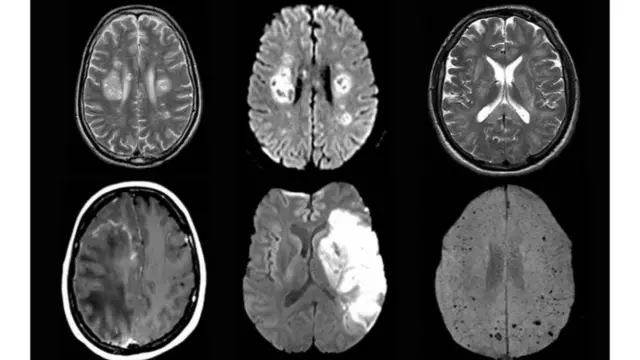

No início de julho, um estudo realizado por pesquisadores da University College London (UCL), do Reino Unido, e publicado na revista científica Brain, indicou que o SARS-CoV-2 causa complicações neurológicas mesmo em pacientes com sintomas leves ou em recuperação, sendo que, muitas vezes, elas não são sequer detectadas ou então o são bem mais tarde.

Os especialistas analisaram 43 pessoas, com idade entre 16 e 85 anos, com confirmação ou suspeita de covid-19. Dessas, 12 sofreram inflamação no sistema nervoso central, dez tiveram encefalopatia transitória (doença cerebral), com sintomas de delírios ou psicose, oito tiveram AVC e, outras oito, problemas nos nervos periféricos, sobretudo com o diagnóstico da Síndrome de Guillain-Barré (SGB), reação imunológica que ataca os nervos e causa paralisia.

Dentre as 12 com inflamação cerebral, nove apresentaram encefalomielite aguda disseminada (ADEM, na sigla em inglês), patologia rara que provoca a destruição degenerativa do sistema nervoso central e afeta os nervos no cérebro e na medula espinhal.

Crédito, University College London

De acordo com o estudo, o vírus causador da covid-19 não foi detectado no líquido cefalorraquidiano, ou fluído do cérebro, de nenhuma das pessoas analisadas, o que sugere que ele não ataca diretamente o órgão para causar a doença neurológica.

No entanto, os pesquisadores encontraram indícios de que a inflamação cerebral provavelmente é causada por uma resposta imune à doença. Segundo eles, mais análises são necessárias para entender exatamente como se dá a relação entre o SARS-CoV-2 e o cérebro.